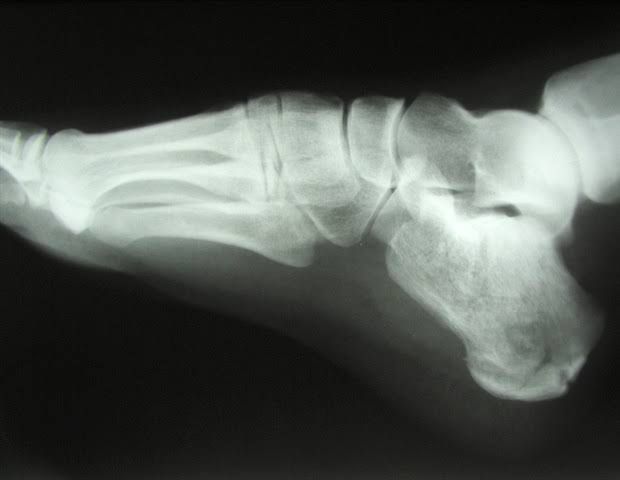

Osteopenia is a loss of bone mineral density (BMD) that weakens bones. It's more common in people older than 50, especially women. Osteopenia has no signs or symptoms, but a painless screening test can measure bone strength. Certain lifestyle changes can help you preserve bone density and prevent osteoporosis.